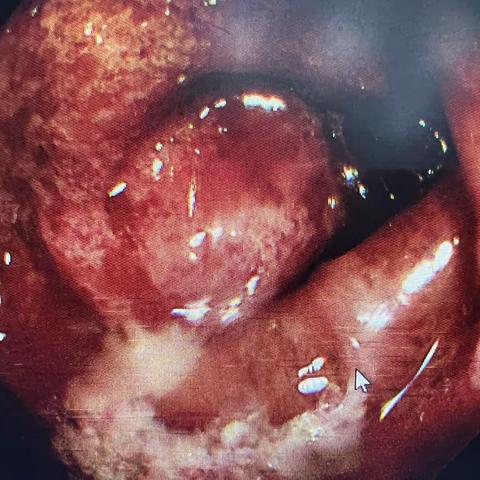

缺血性肠炎?

肠道疾病不能忽视~

哪些人需要做肠镜?

2022-06-13 1107阅读